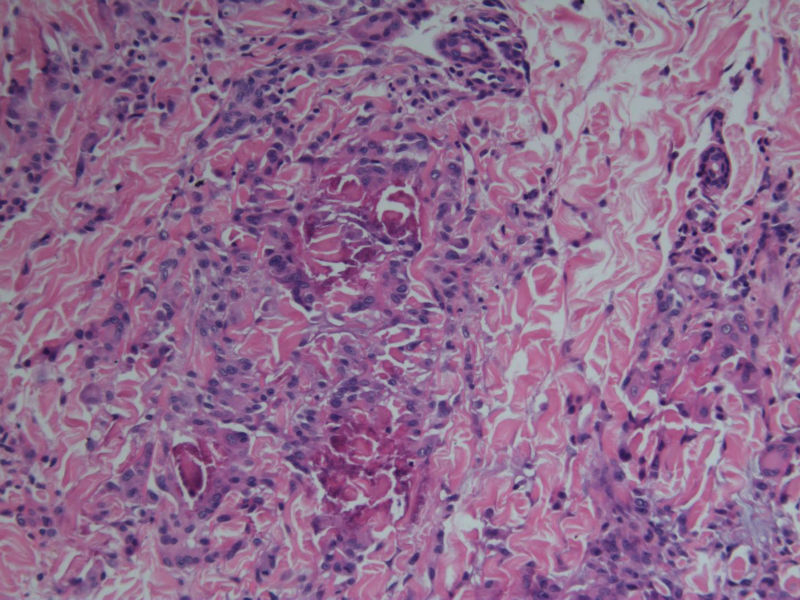

患者 男,8岁,双小腿渐粗红肿伴痒20余天,皮疹渐扩大,且出现硬化萎缩,入院后发现肺吸虫(+)。临床考虑:肺吸虫病硬皮病。请问斑竹大人考虑啥?

• 双小腿红肿伴痒20余天图2

图2

×参考诊断

肺吸虫引起的嗜酸性粒细胞增多性疾病

但镜下没看见嗜酸性粒细胞呀

肉芽肿中央不是凝固性坏死,好像是胶原纤维,否为环状肉芽肿或类脂质渐进性坏死